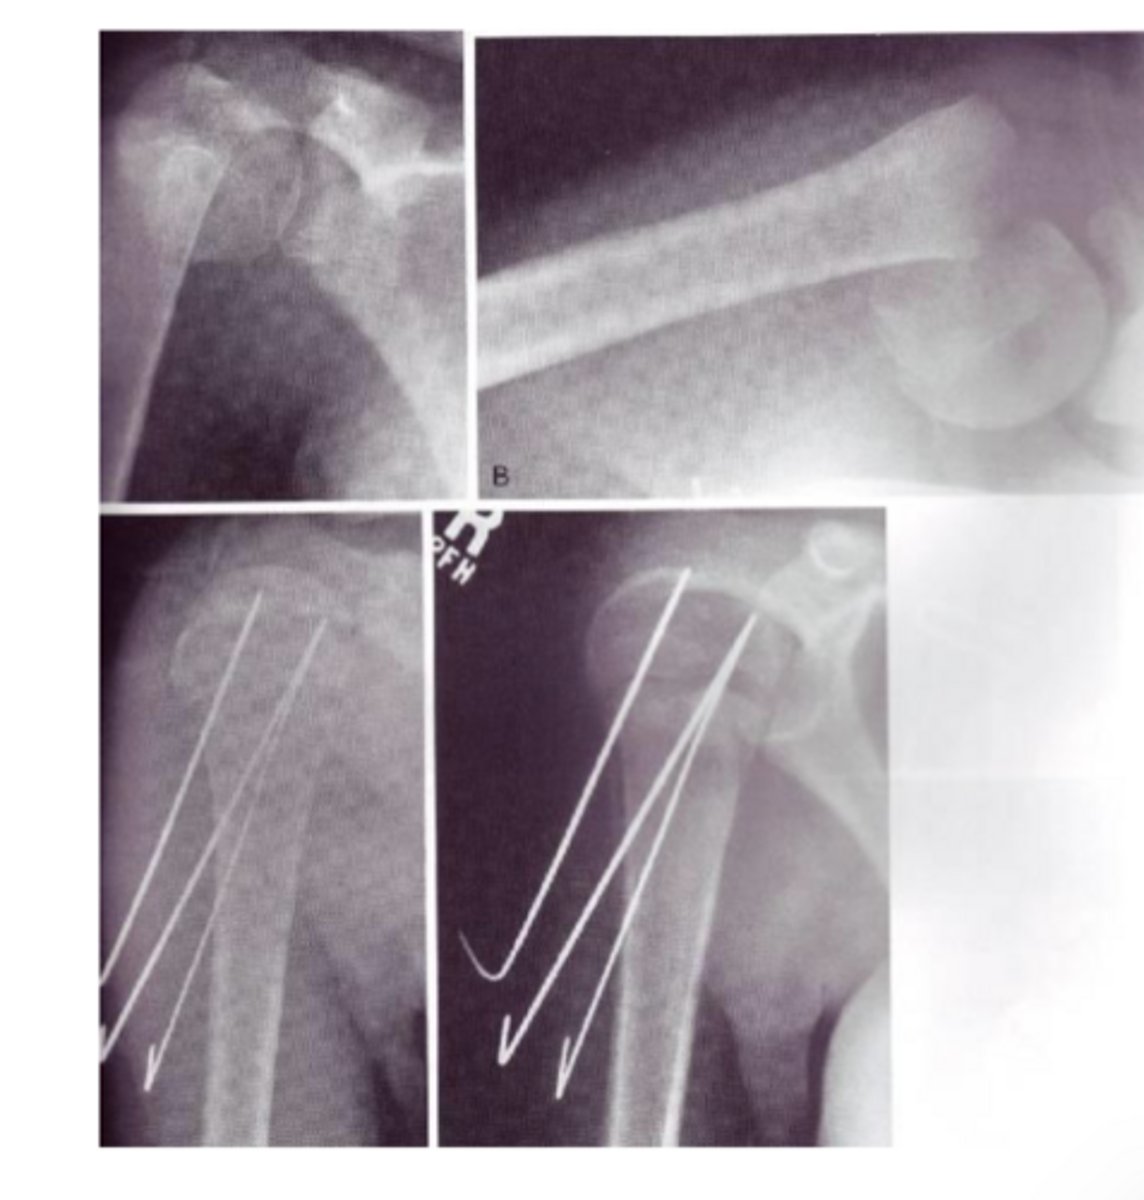

percutaneous fixation

running small pins across the fx

proximal humeras fx

metaphyseal, extra-articular

most are stable and heal well

shoulder and elbow stiffness very common

early motion if possible